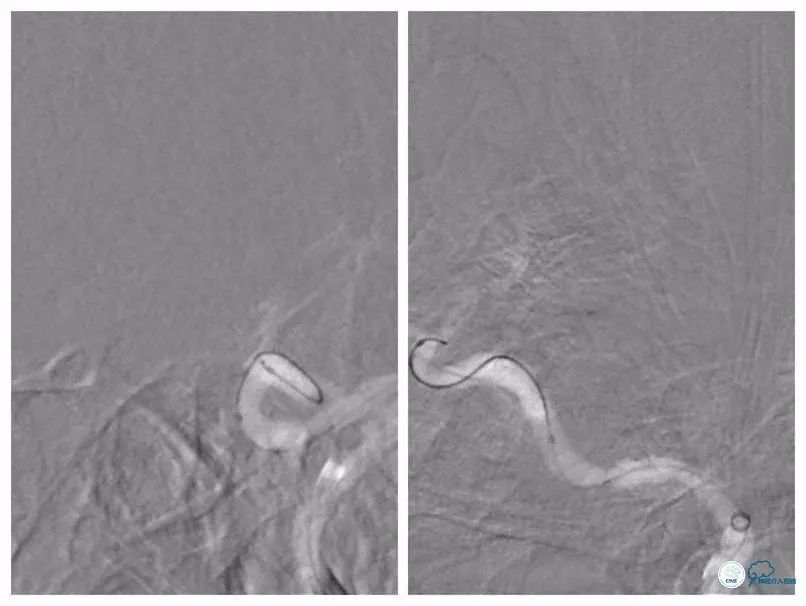

更换为Pilot-50微导丝(0.014″,200cm),越过狭窄起始段,再次更换为Synchro微导丝,送至左大脑中动脉M2段(图9)。

图9

跟进Echelon 10微导管以期通过病变未获成功,遂逐节剪断微导管撤出微导管,保留微导丝。送入Ultra-soft球囊(2.0mm×20mm)至狭窄段近端及远端行球扩后造影显示狭窄程度和前向血流均有所改善(图10)。

图10